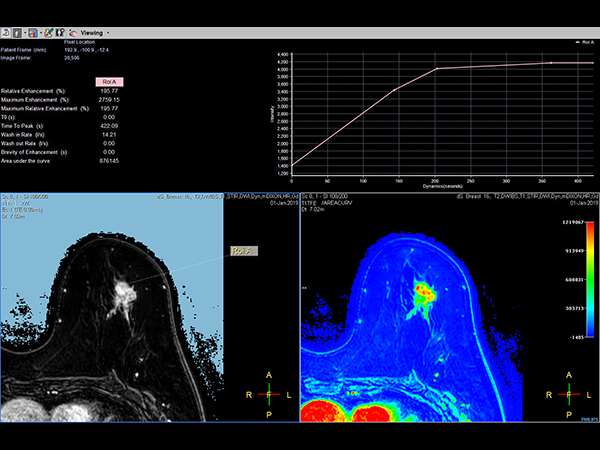

Dynamic 3D mDIXON XD - Post processing Compressed SENSE

-